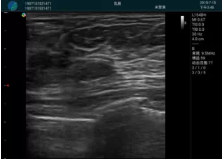

可視化甲狀腺穿刺引導(dǎo)

甲狀腺囊性結(jié)節(jié),囊壁鈣化,透聲好

甲狀腺囊性占位

2001年美國健康護(hù)理研究和質(zhì)量監(jiān)督局(AHRQ)批準(zhǔn)了一項(xiàng)關(guān)于提高患者安全性的報(bào)告,建議:在頸內(nèi)靜脈中心置管術(shù)時使用超聲引導(dǎo)。此后超聲引導(dǎo)穿刺被用于幾乎所有的急診穿刺操作,尤其是血管穿刺。